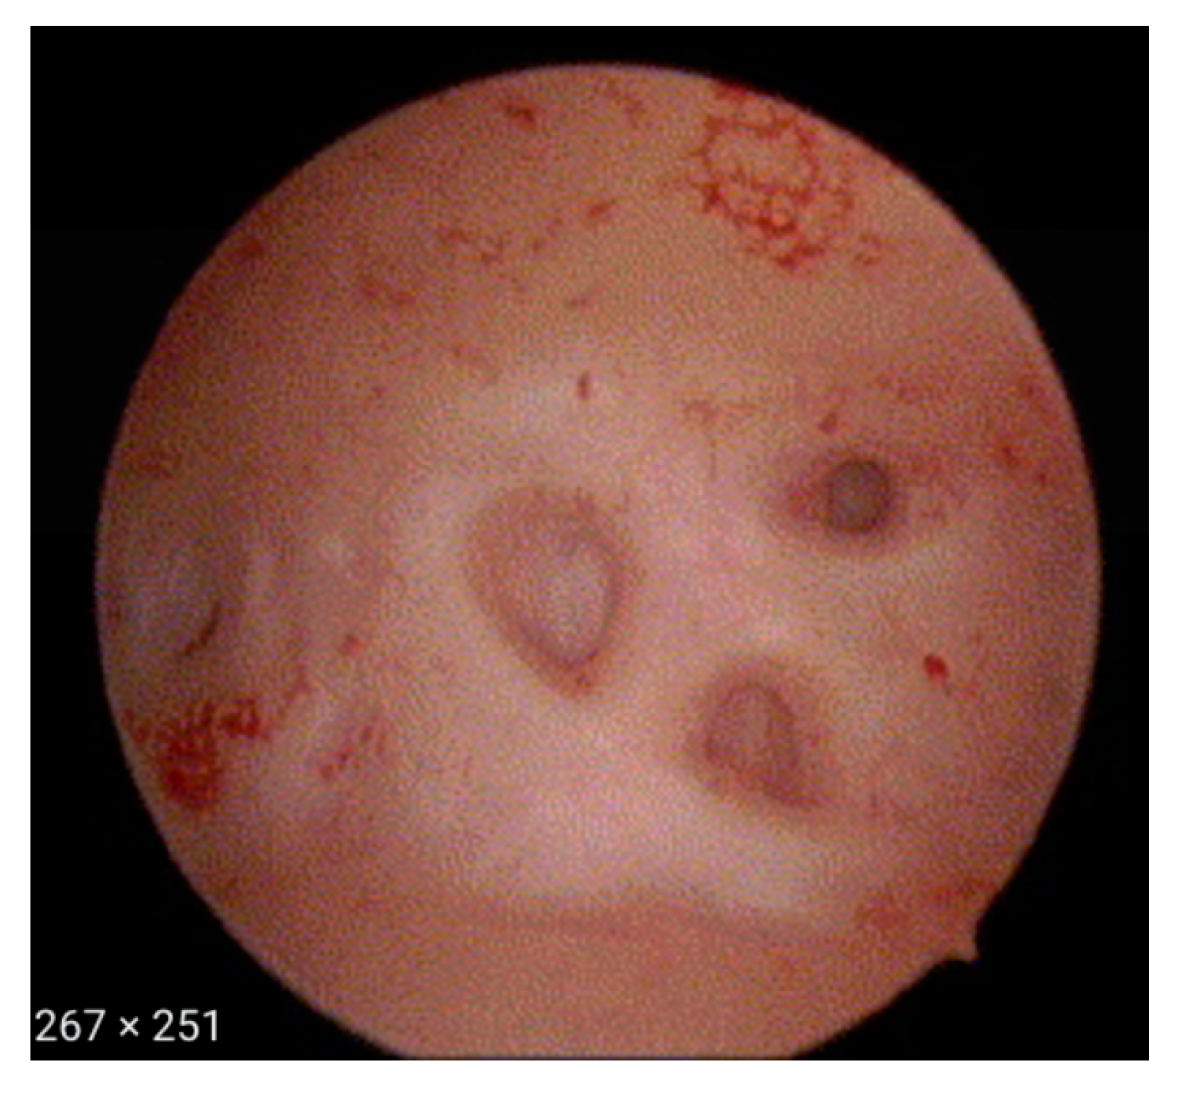

- Irregular endometrium with tiny openings seen on the endometrial surface (Figure 1)

- An endometrial “strawberry” pattern (Figure 3)